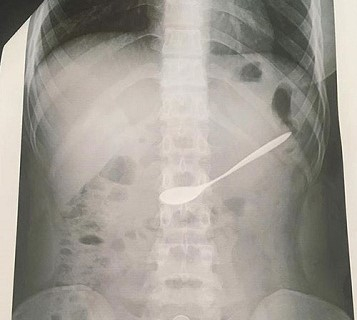

Ngày 10/6, thông tin từ Bệnh viện đa khoa TP Vinh, Nghệ An cho biết, mới đây, các bác sỹ của bệnh viện đã kịp thời cấp cứu, gắp dị vật là một chiếc thìa kim loại ra khỏi bụng nữ bệnh nhân.

Theo đó, trong lúc uống cà phê với bạn, một cô gái 20 tuổi, trú tại TP Vinh, Nghệ An đã không may nuốt chiếc thìa dài khoảng 7cm, bằng kim loại dùng để khuấy cà phê vào trong bụng. Thiếu nữ này đã cố gắng khạc, ho để đẩy chiếc thìa ra ngoài nhưng không được. Sau đó, người bạn đi đã nhanh chóng đưa cô gái tới Bệnh viện đa khoa TP Vinh cấp cứu.

Tại đây, sau khi tiếp nhận, nữ bệnh nhân được chuyển đến phòng Nội soi Tiêu hóa. Kiểm tra các bác sĩ phát hiện chiếc thìa bằng kim loại đang nằm trong dạ dày của nữ bệnh nhân. Rất may chiếc thìa không có cạnh sắc nhọn nên không gây tổn thương. Sau khi chẩn đoán, các bác sỹ của bệnh viện đã tiến hành gắp chiếc thìa cà phê ra khỏi người bệnh nhân.